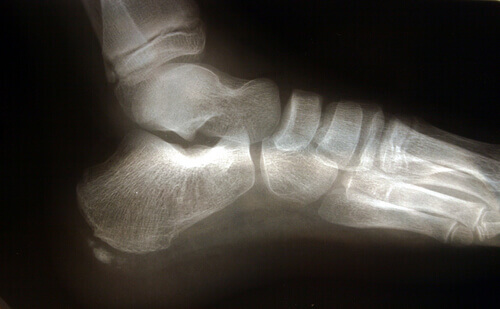

Topuk dikeni sıklıkla kemik çıkıntılarının varlığı ile ilişkilendirilir.